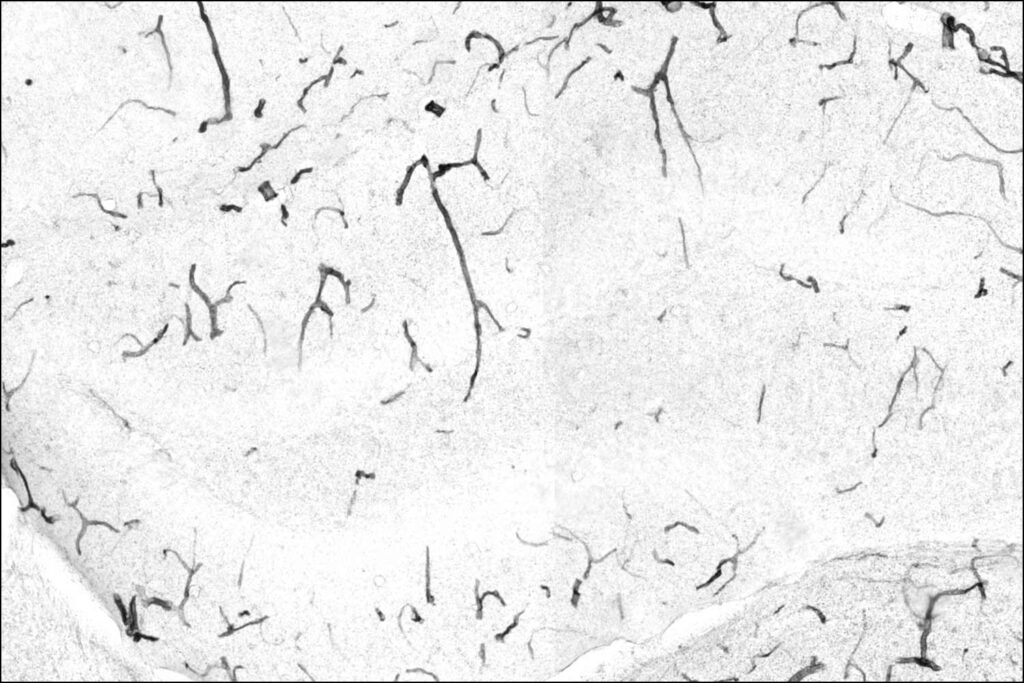

In the team’s model, the key downstream player is TNAP, a protein that accumulates on the cells that form the blood-brain barrier as mice age. That buildup, the researchers report, makes the barrier leaky. Exercise changes the equation: liver-produced GPLD1 travels to the vessels surrounding the brain and trims TNAP off the cells, helping “shore up” the barrier.

To track how GPLD1 might be working, the scientists focused on the enzyme’s core role—cutting certain proteins off cell surfaces—and searched for tissues where these targets might accumulate with age. The blood-brain barrier stood out. When the researchers tested several potential targets in lab experiments, they found GPLD1 only cut one of them: TNAP.